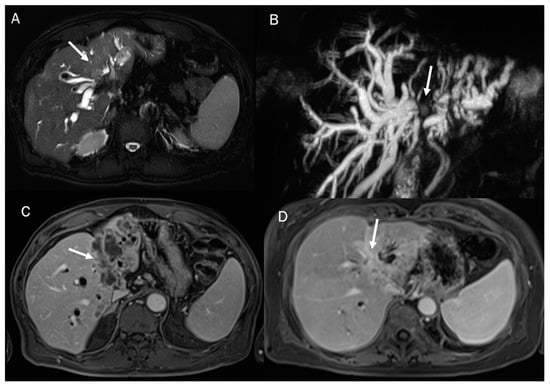

Mass-forming ICC usually appears at basal CT as a hypodense lesion presenting either a well-defined border or an infiltrative pattern without its own capsule (Figure 4). It is associated with heokpatic capsule retraction in about 20% of cases [108,109]. After contrast administration, the nodule shows initial peripheral rim enhancement, followed by progressive and concentric filling with contrast material as an effect of fibrosis, which is slow to enhance but retains the intravenous contrast agent [110,111].

Figure 4.

CT assessment of ICC (arrow) during arterial (A) and portal (B) phase of contrast study. The lesion (arrow) shows an infiltrative pattern with biliary tree dilatation.